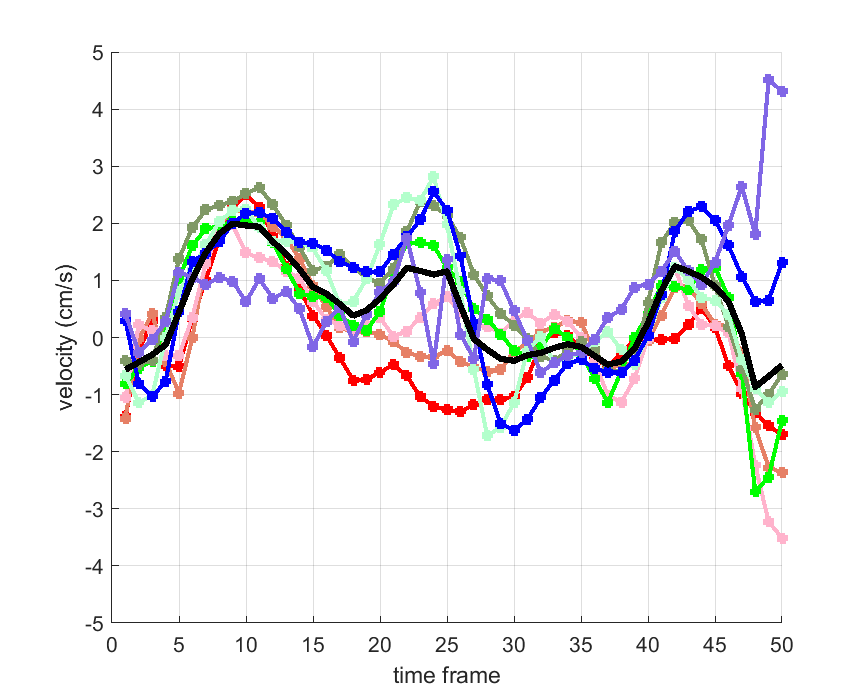

Time courses of the estimated translational component per subject, frame, slice and volume along the 3 velocity directions x, y and z are presented in Fig.6 - Fig.8.